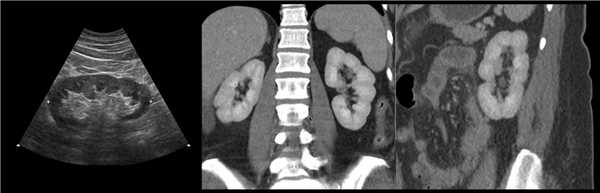

(Левый) Продольный ультразвуковой срез правой почки, визуализируется гипертрофирован ная бертиниева колонна, изоэхогенная корковому веществу почки.

(Правый) МРТ с контрастным усилением у этого же пациента (по поводу другого заболевания почки; не показано), визуализируется очаг такой же интенсивности сигнала, как и корковое вещество почки, сравнимое с гипертрофированной бертиниевой колонной.

3. КТ при бертиниевых колоннах почки:

• Бесконтрастная КТ:

о Связаны с корковым веществом

о Боковое вдавление синуса почки

о Деформированные смежные чашечки и воронка

• КТ с контрастированием:

о Отсутствие объемного образования

о Контрастирование аналогично нормальному корковому веществу:

- Лучшая визуализация в кортико-медуллярную фазу

- При недостаточной информативности аксиальной проекции эффективна коронарная реконструкция

(Слева) На рисунке показано объемное расширение коркового вещества почки между верхней и средней чашечками.

(Справа) КТ, аксиальная проекция, кортико-медуллярная фаза контрастирования: дорсальная половина межполюсной области почки, контрастируемая аналогично корковому веществу почки. На последующих фазах выявлено гомогенное контрастирование почки.

(Слева) УЗИ, продольная плоскость сканирования: гипоэхогенное «объемное образование» в центре, которое выступает в почечную лоханку.

(Справа) КТ с контрастированием, аксиальная проекция: у этого же пациента установлено, что «объемное образование» — это нормальное корковое вещество почки, которое инвагинирует в почечную лоханку между чашечками верхнего полюса и меж полюсной областью почки. Обратите внимание на нормальный внешний контур почки. Бертиниевы колонны чаще всего выявляют с одной стороны и слева, как в данном случае: в 18% случаев они могут быть двусторонними.